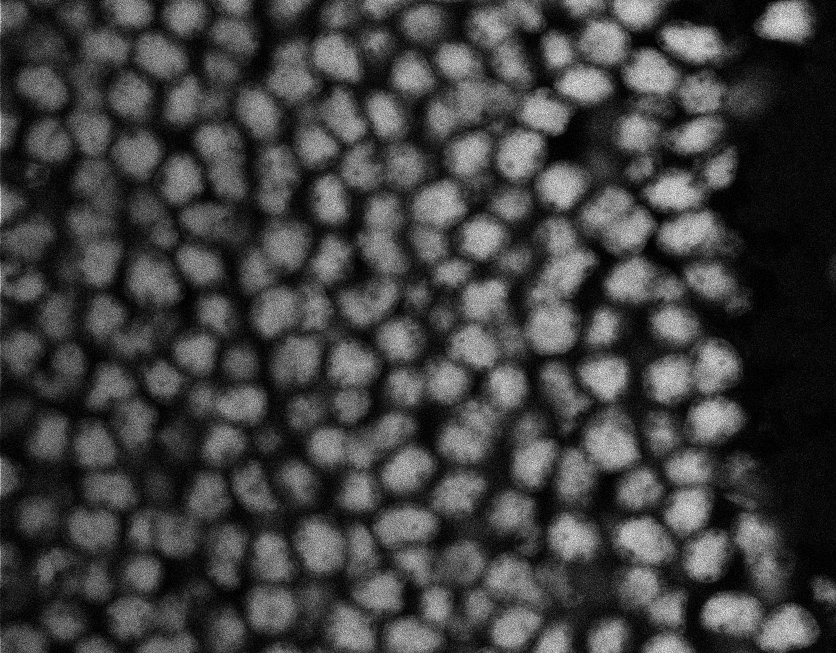

Actin

Nuclei